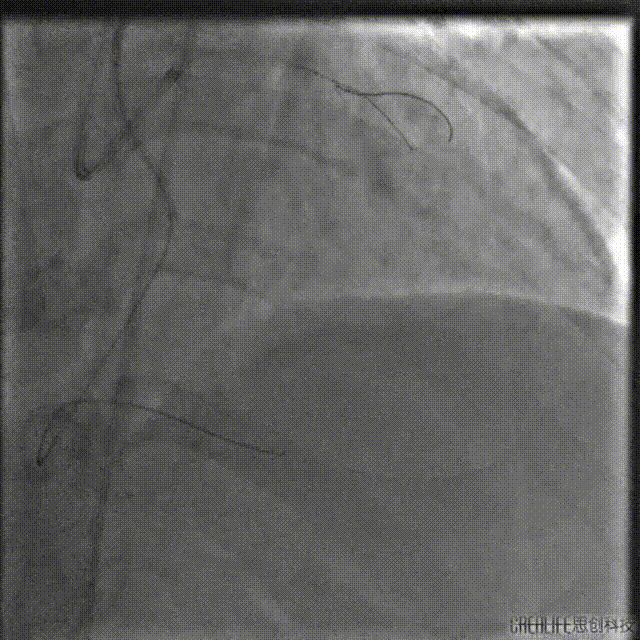

微导管辅助下尝试正向开通

左冠:7Fr EBU3.5;右冠:7Fr AL1.0;Runthrough导丝送至RCA远端,LAD送P200导丝在微导管支撑下进入CTO病变体部。

P200导丝反复调整仍无法突破CTO病变远段,遂走行至D1,通过逆向造影进一步确认。

送入双腔微导管增强支撑,并送入第二根P200导丝继续尝试正向进攻,未能进入LAD中段真腔。

撤出微导管,1.5mm球囊扩张LAD近段后,送入IVUS导管,明确LAD近段导丝是否走行在真腔内,观察LAD在D1分叉处的开口位置,指导CTO导丝的进攻方向。

回撤显示导丝位于真腔,分叉处CTO入口在11-12点处,遂在X线影像中标记入口位置。

重新送入双腔微导管及P200导丝,在CTO入口处尝试进入远端真腔,但反复调整导丝仍未成功。